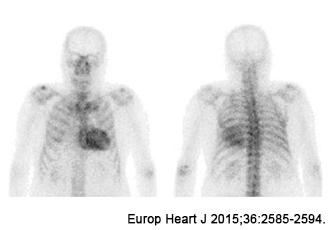

Myocardial scintigraphy

This test allows us to assess blood flow to the heart muscle, the extent of myocardial necrosis, and cardiac function. By examining changes in blood flow during exercise or other stress tests, we can obtain information about angina and areas of insufficient blood flow.

Pyrophosphoric myocardial scintigraphy is highly accurate and frequently used for the diagnosis of cardiac amyloidosis.